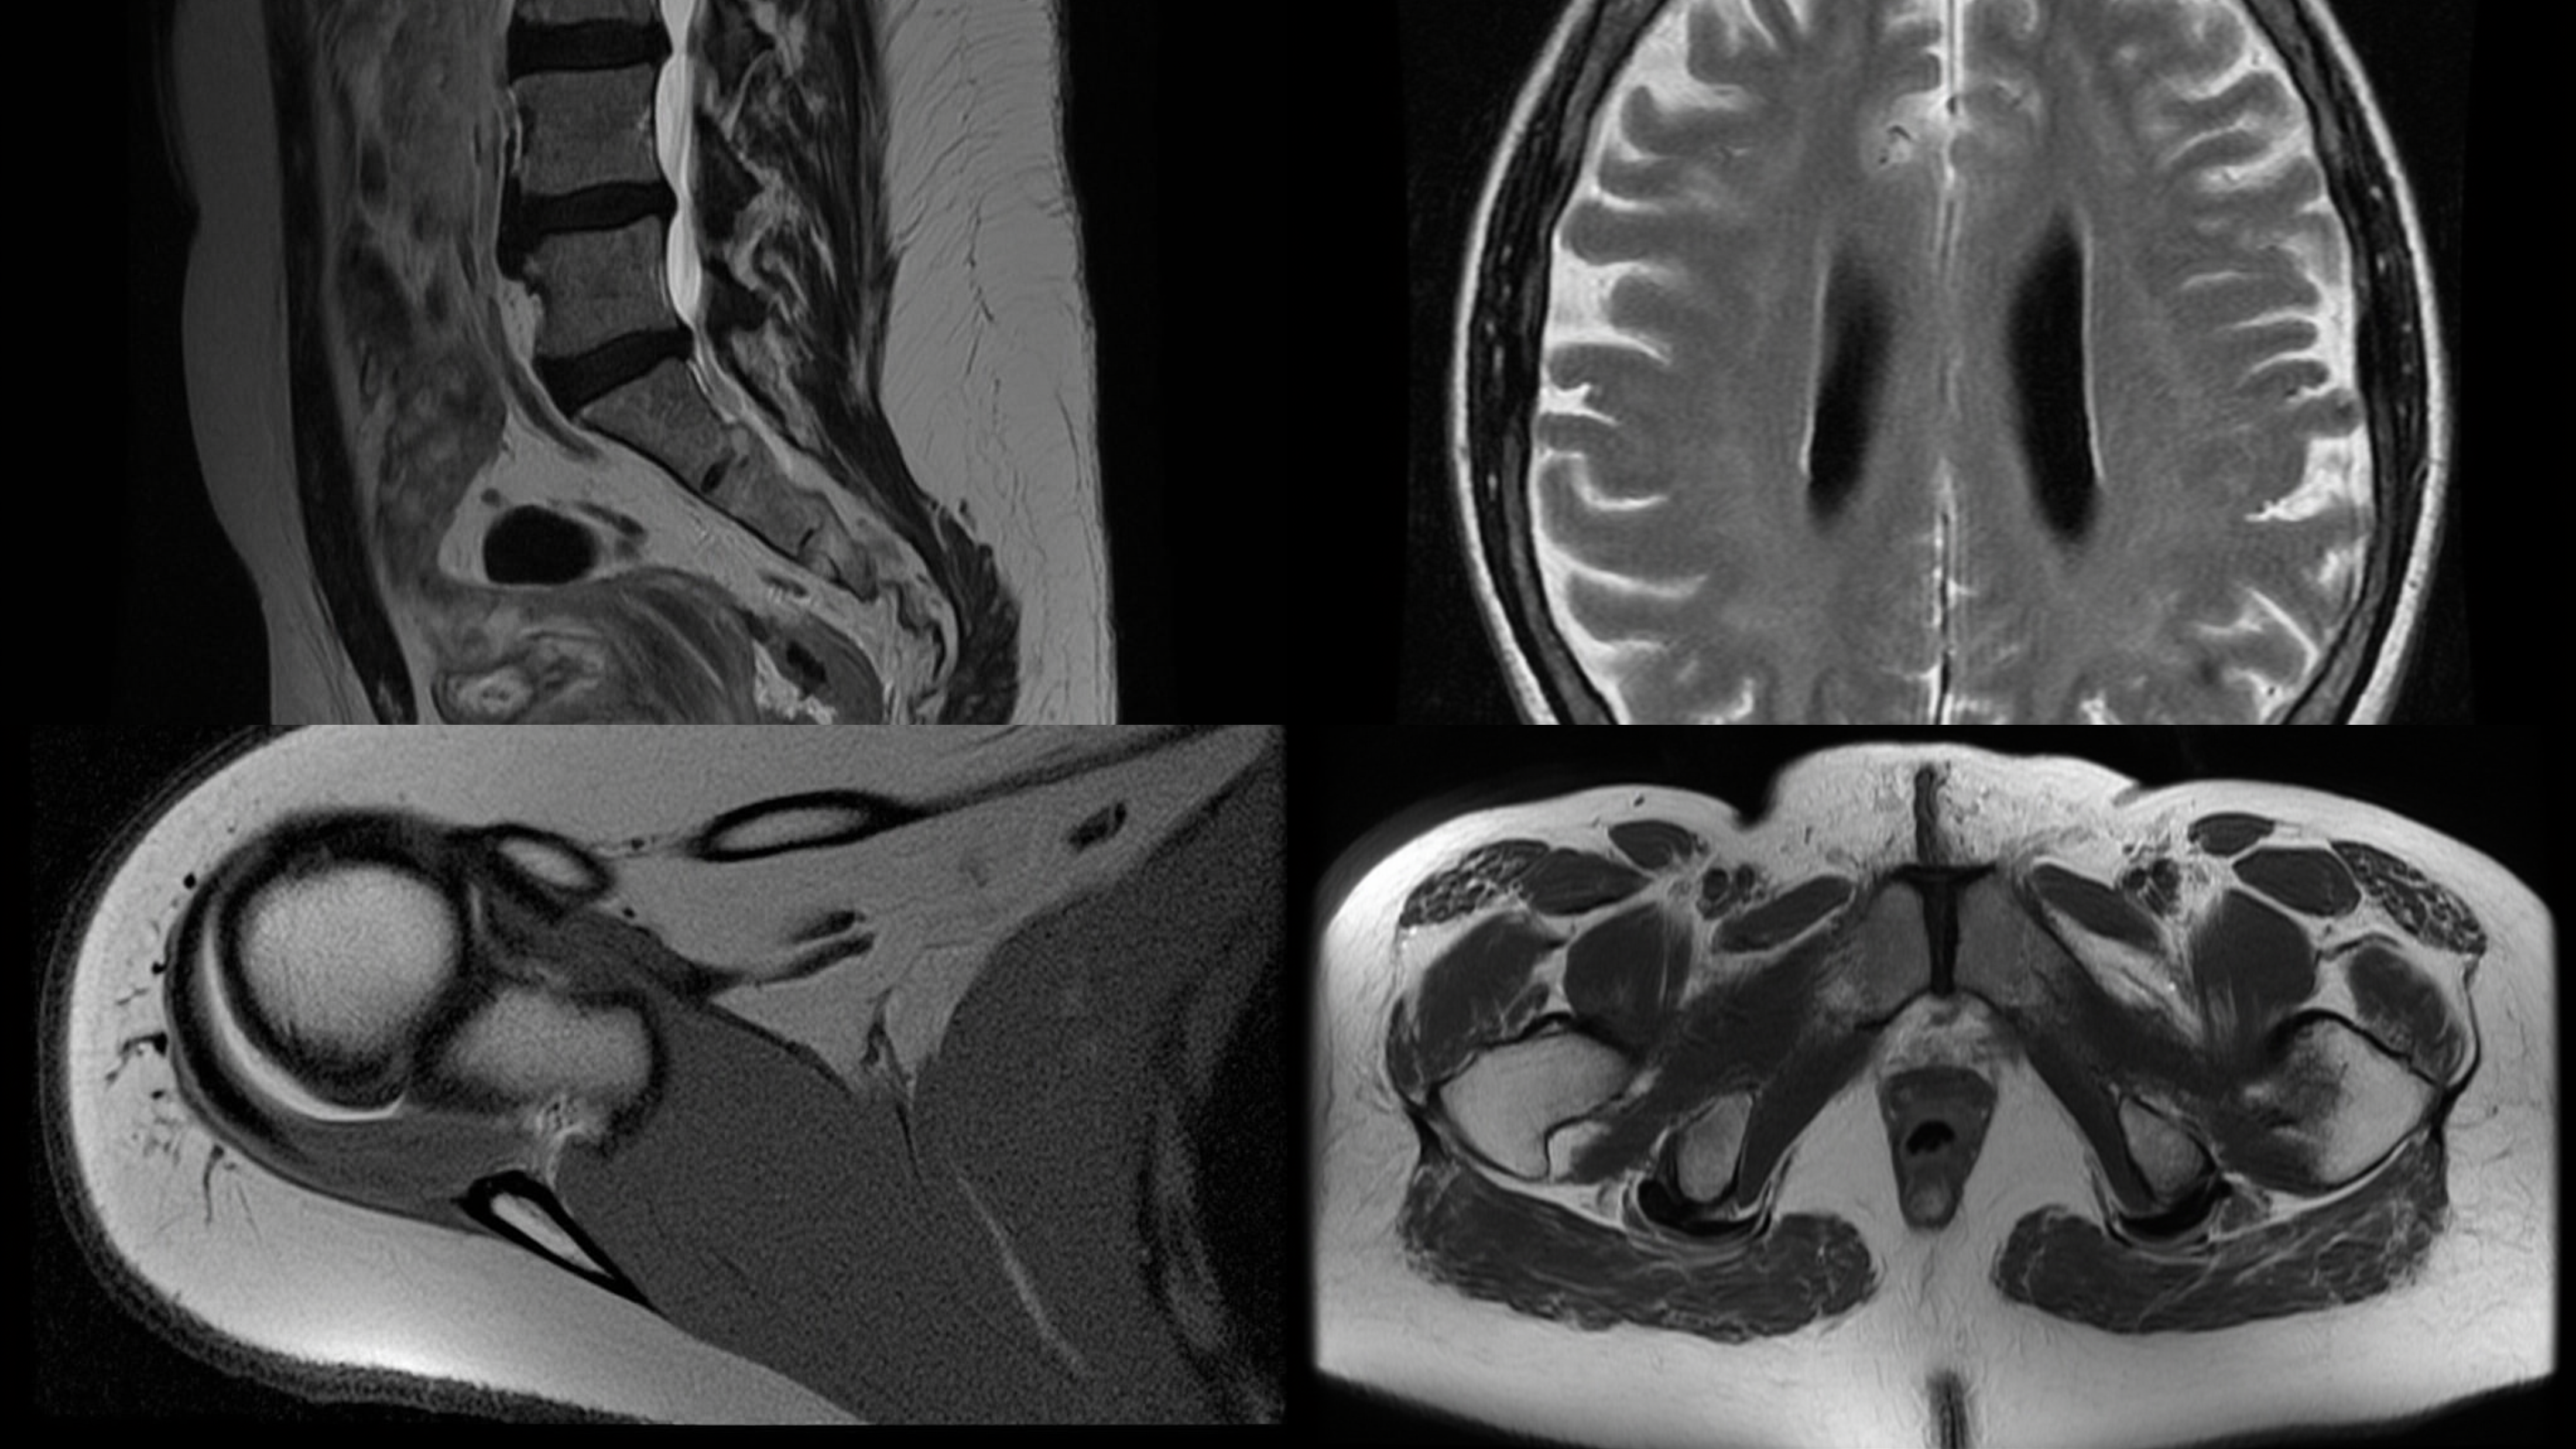

Magnetic Resonance Imaging (MRI)

MRI Scan